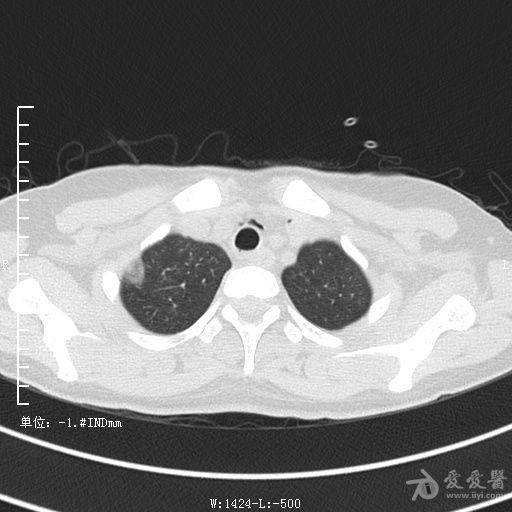

典型支气管扩张及肺水肿CT片

典型支气管扩张肺水肿